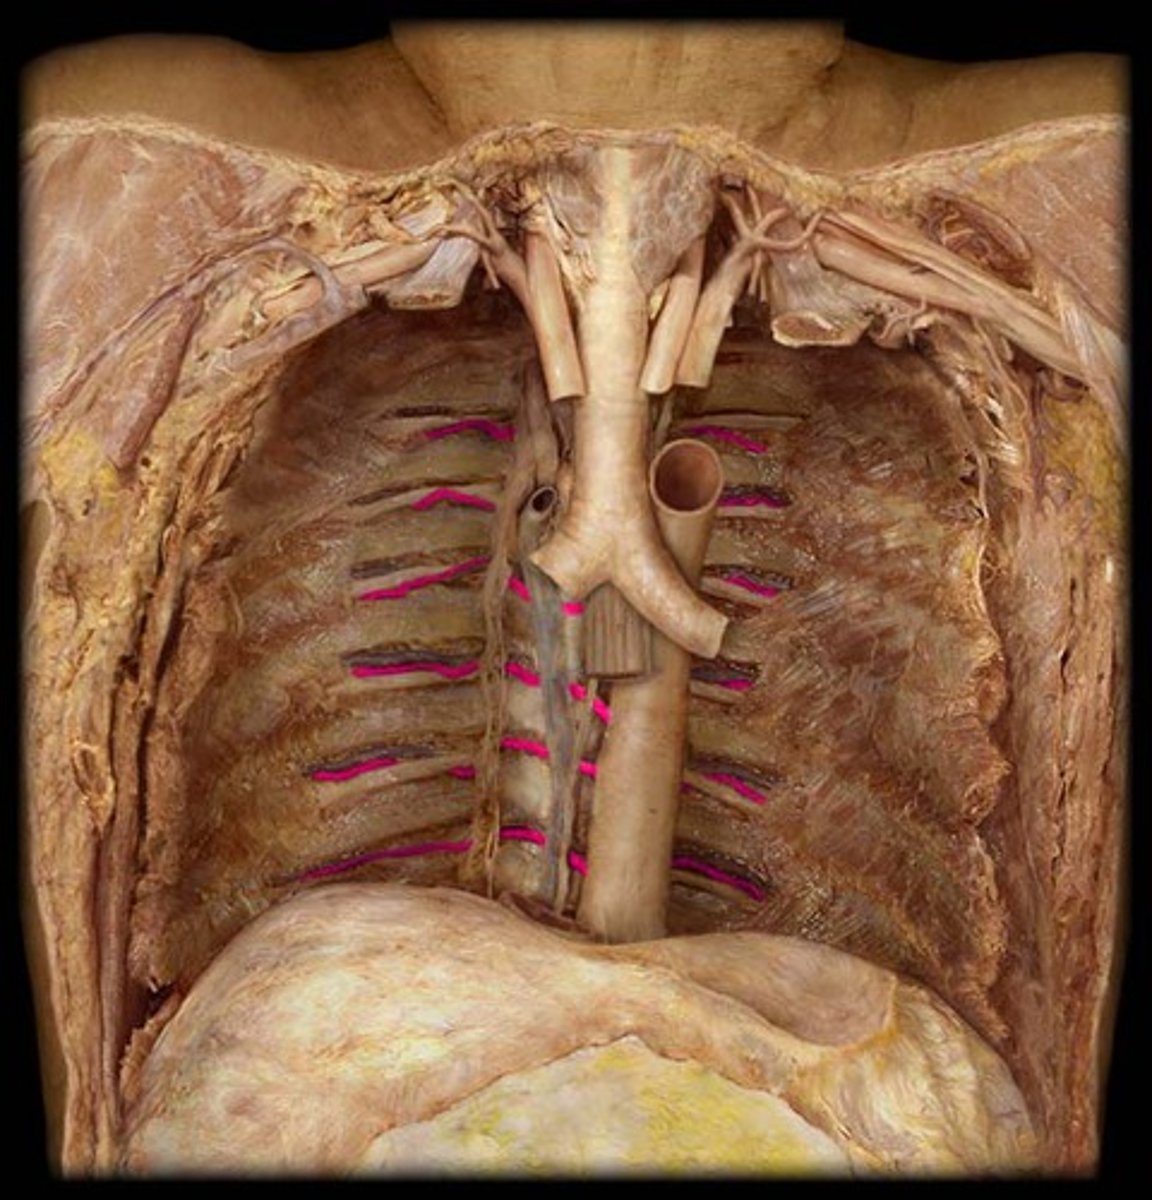

R. internal thoracic artery

runs deep to the costal cartilages to supply the anterior chest walls

L. internal thoracic artery

comes off the l. subclavian, going towards the thorax

thoracic aorta

travels downward through the thorax

left posterior intercostal arteries

enters the 3rd through 11th intercostal spaces, supplies the chest wall